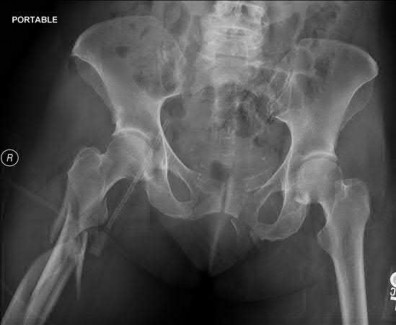

Question 1:

A 35-year-old male is brought to the trauma bay after a severe fall from height. He is hypotensive and tachycardic. An AP pelvis radiograph demonstrates a vertically displaced left hemipelvis with severe disruption of the posterior sacroiliac complex and symphysis pubis. If active arterial hemorrhage is identified on angiography, which vessel is most likely injured in this specific injury pattern?

Options:

- Obturator artery

- Internal pudendal artery

- Superior gluteal artery

- Corona mortis

- Inferior epigastric artery

Correct Answer: Superior gluteal artery

Explanation:

Vertical shear pelvic fractures involve massive disruption of the posterior pelvic ring, including the sacrotuberous and sacrospinous ligaments. The superior gluteal artery exits the pelvis through the greater sciatic notch in close proximity to the sacroiliac joint and is the most commonly injured artery in vertical shear pelvic fractures. In contrast, APC (Anteroposterior Compression) injuries are more typically associated with injuries to the internal pudendal and obturator arteries.